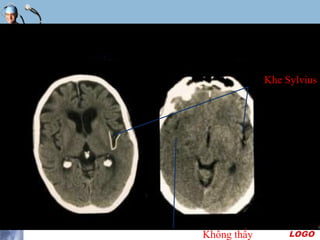

Mờ khe Sylvius

 Khe Sylvius được nhận rõ trên hình CT nhờ chứa dịch

não tủy

 Khi thùy đảo bị phù nề thì lớp dịch này giảm bề dầy hay

mất hẳn nên không còn phân biệt được

 Dấu hiệu này thường đi kèm dấu mờ nhân đậu và dấu

ru băng thùy đảo

Khe Sylvius

Không thấy